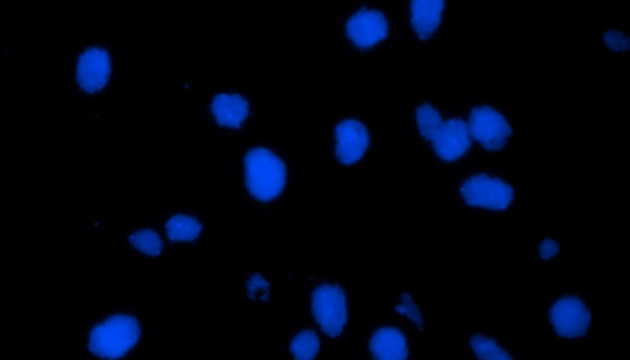

熒光原位雜交(Fluorescence In Situ Hybridization,F(xiàn)ISH)是臨床病理檢測(cè)中廣泛運(yùn)用的一種分子細(xì)胞遺傳學(xué)診斷技術(shù),其原理是用熒光染料直接或間接標(biāo)記的DNA核酸探針與待測(cè)樣本中的DNA核酸序列按照堿基互補(bǔ)配對(duì)的原則進(jìn)行雜交,然后通過熒光顯微鏡觀察熒光信號(hào)位置、數(shù)量等來判斷待測(cè)序列的缺失、擴(kuò)增及易位等情況。其高分辨率、直接反映異常細(xì)胞比例、快速簡(jiǎn)便的特點(diǎn),使其成為臨床檢測(cè)、預(yù)后評(píng)估及用藥指導(dǎo)的重要工具。

FISH技術(shù)面臨熒光弱、背景噪聲、多通道疊加等難點(diǎn)。為了保障熒光信號(hào)強(qiáng)度,一般需要用到研究級(jí)熒光顯微鏡,半復(fù)消色差或以上的物鏡,以及高功率的LED熒光光源或汞燈光源;為了去除背景噪聲,一般需要搭配高截止深度的濾光片和高靈敏度相機(jī);多通道疊加時(shí)要提取紅綠信號(hào)點(diǎn),然后放到藍(lán)色DAPI信號(hào)上,處理需要相當(dāng)?shù)募记伞?